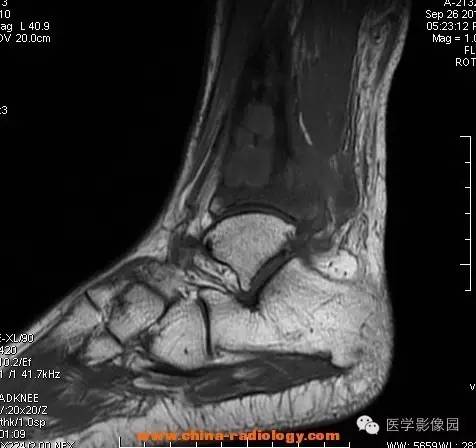

影像学表现:胫骨中下段干骺端不未规则形长T1长T2信号,T2WI见不完整环形稍低信号影,T2脂肪抑制低信号更明显,并见胫骨下段及踝关节后外侧软组织呈弥漫稍高信号,增强明显不均匀强化,增强见低信号环内有环形强化影。

影像学表现:表现为长骨干骺端有椭圆形密度减低区,边缘有清晰的骨质硬化,病变与邻近正常骨髓腔境界清楚。MRI上T1WI呈低信号,少数呈等信号,T2WI多为混杂高信号,增强扫描可见环状强化,强化的脓肿壁薄而均匀。